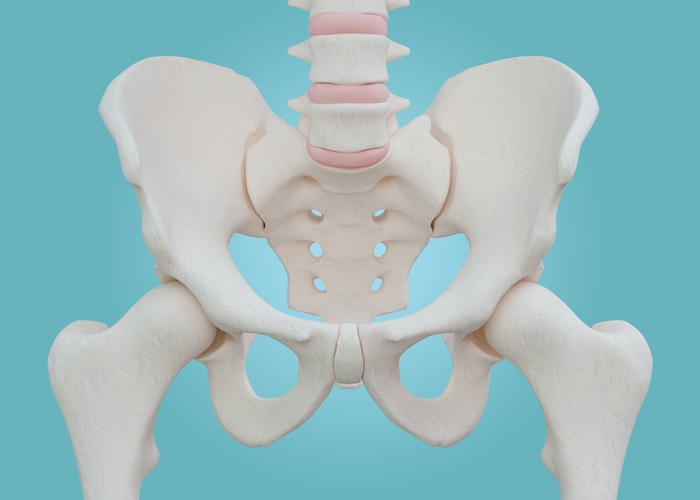

고관절 수술 유형

고관절 수술에는 여러 가지 유형이 존재합니다. 각각의 수술은 서로 다른 접근 방식을 가지고 있으며, 회복 기간 및 필요한 관리 방법이 상이합니다.

- 인공관절 치환술: 가장 일반적인 고관절 수술입니다. 퇴행성 관절염이나 심한 외상으로 인해 고관절이 손상된 경우, 인공 관절로 대체합니다. 이 수술은 대개 1-2시간 가량 소요되며, 회복이 길어질 수 있습니다.

- 관절경 수술: 최소침습 수술 방식으로, 작은 절개로 카메라와 기구를 삽입해 손상된 조직을 치료합니다. 회복 기간은 일반적으로 짧지만, 재활이 중요합니다.

- 고관절의 재건 수술: 이를 통해 고관절의 기능을 복원할 수 있습니다. 주로 젊은 환자에게 시행되며, 회복 과정에서 신체의 자연 치유 과정을 중요하게 생각해야 합니다.

각 수술 방식에 따라 환자의 상태를 고려한 특화된 치료 계획이 필요합니다. 예를 들어, 인공관절 치환술을 받을 경우에는 십여 주의 회복 기간 동안 물리 치료와 약물 치료가 반드시 포함되어야 합니다. 반면 관절경 수술의 경우에는 초기 회복 단계에서의 가벼운 운동과 체중 부하가 더 강조될 수 있습니다.